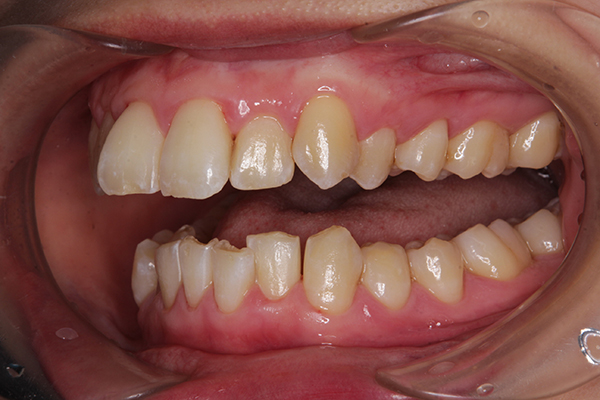

既に、食事の時の噛み合わせも変化していました。

マウスピースをはめているときに

噛み合わせると普通なのに、マウスピースを外してカチカチ噛むと

もう既に矯正前の噛み合わせではなくなっていて

改めて矯正ってすごいなぁと感動しました。